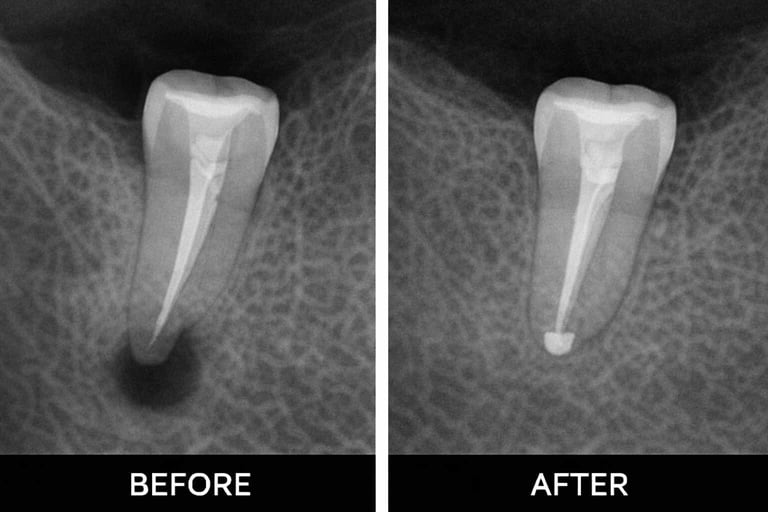

Examination & X-rays – determine the extent of infection or damage

Shaping & filling – shape canals and fill with biocompatible material